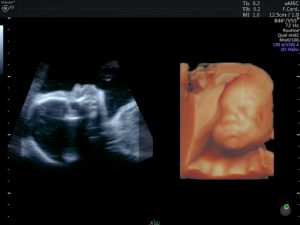

Normal fetal echocardiogram at 16 weeks gestation

NORMAL 4 CHAMBER HEART AT 16 WEEKS